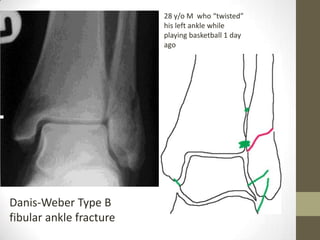

28 y/o M who “twisted”

his left ankle while

playing basketball 1 day

ago

Danis-Weber Type B

fibular ankle fracture